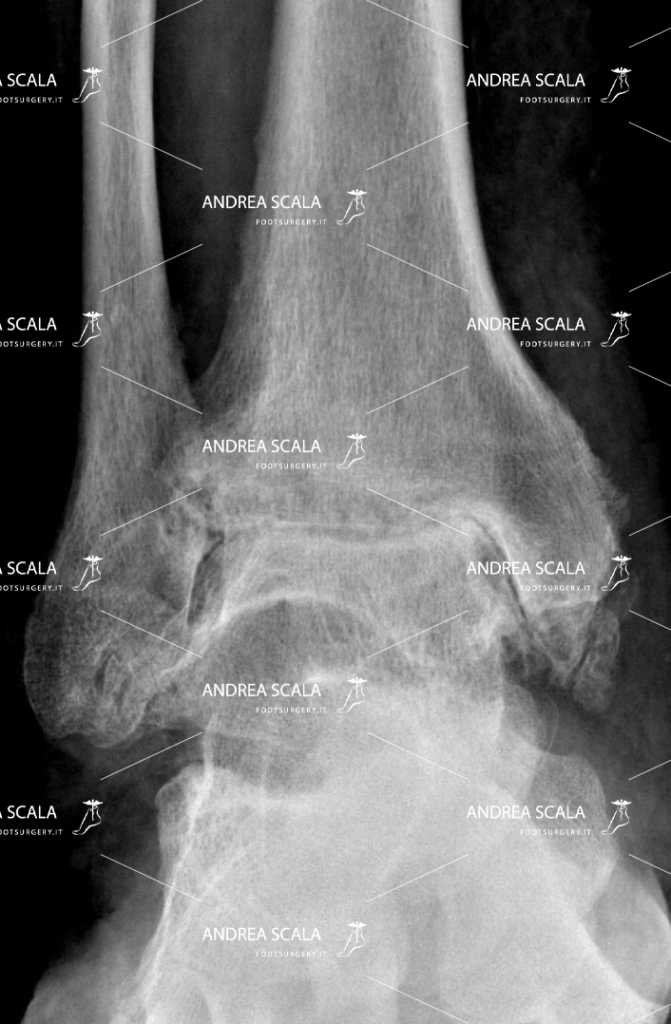

Ma cos’è esattamente l’artrosi della caviglia? Come si manifesta? Da cosa è causata? Prima di vederla nel dettaglio, è opportuno fare alcuni cenni sull’artrosi in generale. Questa patologia degenerativa, denominata anche osteoartrosi, può colpire tutte le articolazioni, le caviglie non fanno eccezione. L’ARTROSI E’ LA SCOMPARSA DELLA CARTILAGINE. La cartilagine separa le ossa e le fa scorrere senza attrito. La cartilagine viene distrutta dopo un incidente o un trauma. Oppure la cartilagine viene consumata dal reumatismo articolare.

In poche parole, l’artrosi è la scomparsa della cartilagine. La cartilagine separa le ossa e le fa scorrere senza attrito. Questa viene distrutta dopo un incidente o un trauma, oppure viene consumata dal reumatismo articolare.

L’artrosi fa sì che il nostro organismo crei un nuovo tessuto osseo (osteofiti) intorno ai legamenti interessati, il quale diventerà via via sempre più duro, causando appunto rigidità, difficoltà di movimento e dolore.

Dopo l’intervento di protesi di caviglia le ossa sono separate. Il movimento della caviglia è tornato normale e senza dolore.